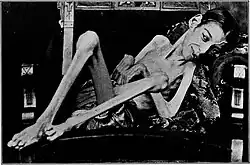

Disuse causes rapid muscle atrophy and often occurs during injury or illness that requires immobilization of a limb or bed rest. Depending on the duration of disuse and the health of the individual, this may be fully reversed with activity. Malnutrition first causes fat loss but may progress to muscle atrophy in prolonged starvation and can be reversed with nutritional therapy. In contrast, cachexia is a wasting syndrome caused by an underlying disease such as cancer that causes dramatic muscle atrophy and cannot be completely reversed with nutritional therapy. Sarcopenia is age-related muscle atrophy and can be slowed by exercise. Finally, diseases of the muscles such as muscular dystrophy or myopathies can cause atrophy, as well as damage to the nervous system such as in spinal cord injury or stroke. Thus, muscle atrophy is usually a finding (sign or symptom) in a disease rather than being a disease by itself. However, some syndromes of muscular atrophy are classified as disease spectrums or disease entities rather than as clinical syndromes alone, such as the various spinal muscular atrophies.

The predominant symptom is increased weakness which may result in difficulty or inability in performing physical tasks depending on what muscles are affected. Atrophy of the core or leg muscles may cause difficulty standing from a seated position, walking or climbing stairs and can cause increased falls. Atrophy of the throat muscles may cause difficulty swallowing and diaphragm atrophy can cause difficulty breathing. Muscle atrophy can be asymptomatic and may go undetected until a significant amount of muscle is lost.[2]

Outcomes of muscle atrophy depend on the underlying cause and the health of the patient. Immobility or bed rest in populations predisposed to muscle atrophy, such as the elderly or those with disease states that commonly cause cachexia, can cause dramatic muscle atrophy and impact on functional outcomes. In the elderly, this often leads to decreased biological reserve and increased vulnerability to stressors known as the "frailty syndrome."[3] Loss of lean body mass is also associated with increased risk of infection, decreased immunity, and poor wound healing. The weakness that accompanies muscle atrophy leads to higher risk of falls, fractures, physical disability, need for institutional care, reduced quality of life, increased mortality, and increased healthcare costs.[3]